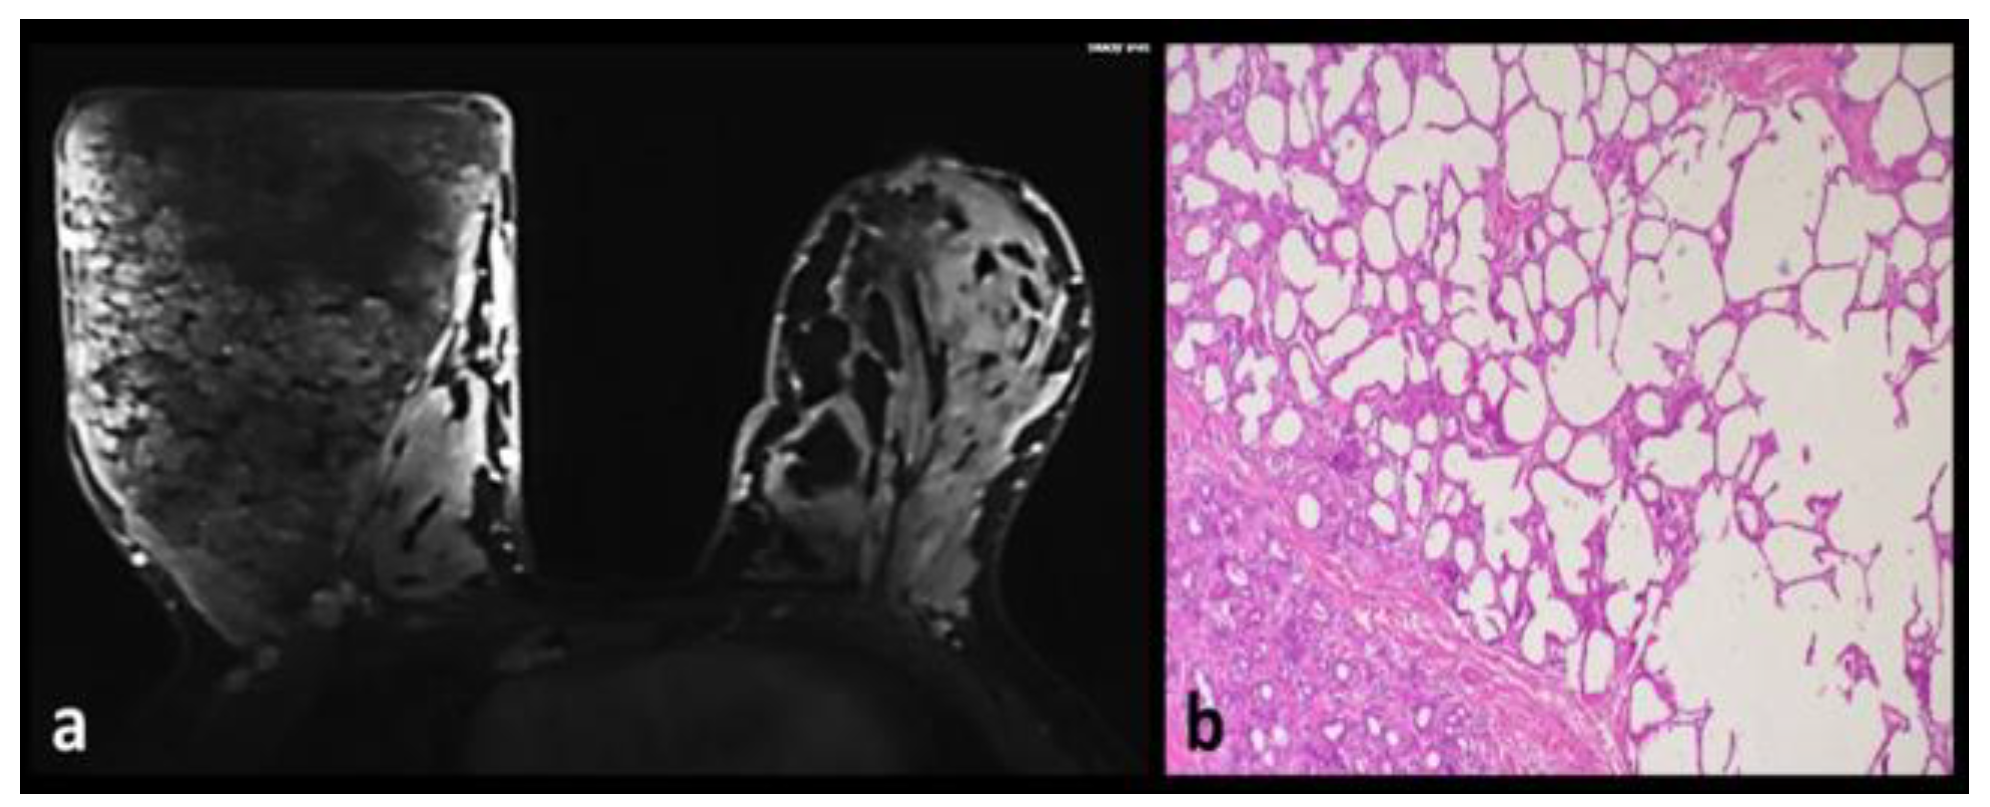

Unilateral Lactation

Sclerosing Adenosis